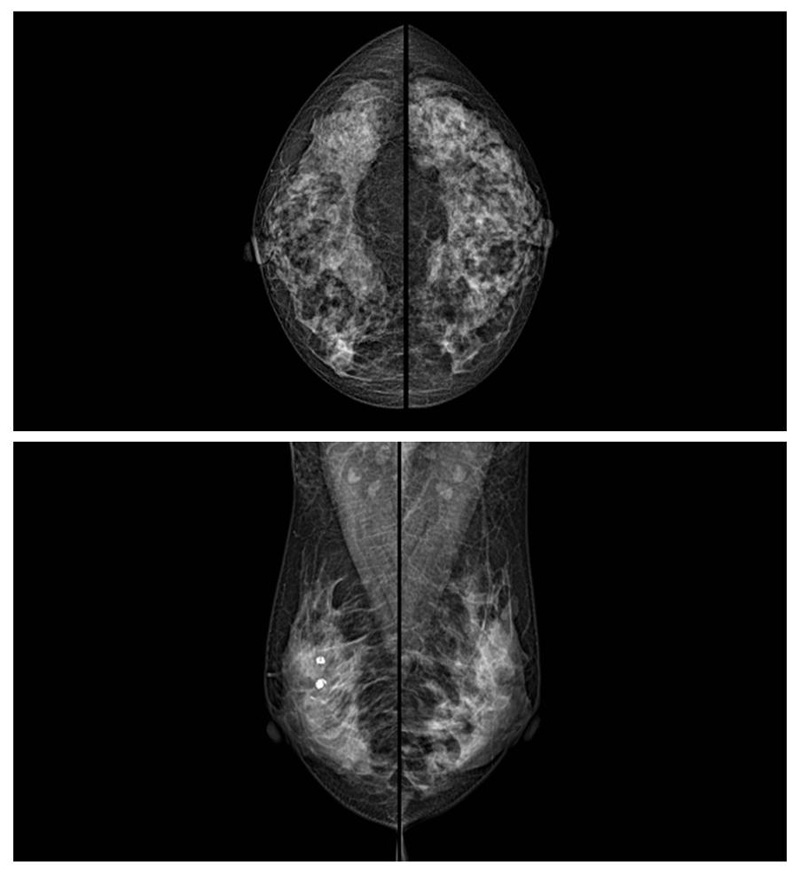

乳腺癌的發(fā)生率越來(lái)越高,已經(jīng)是我們國(guó)家的癌癥之一已成為女性健康“頭號(hào)殺手”。乳腺DR可提高乳腺癌早期檢出率并精準(zhǔn)定位。發(fā)現(xiàn)和診斷早期乳腺癌最有效的方法之一,明顯利大于弊女性都要重視乳腺的檢查。輻射很小最簡(jiǎn)便、最可靠、無(wú)創(chuàng)性檢查手段,做一次乳腺DR的劑量相當(dāng)于7周的正常生活。尤其是對(duì)于40歲以上的女性尤為重要,那么乳腺DR是怎么進(jìn)行檢查的呢?我們來(lái)了解一下,為廣大朋友在檢查前有點(diǎn)心理準(zhǔn)備。檢查時(shí)候是避開經(jīng)期的前后,月經(jīng)來(lái)后的7天左右比較合適。需要脫衣服檢查,根據(jù)拍片的擺位要求,有頭尾位置,內(nèi)外斜位,還有側(cè)位。定點(diǎn)放大壓迫方法可以更細(xì)微清晰的檢查出病灶。